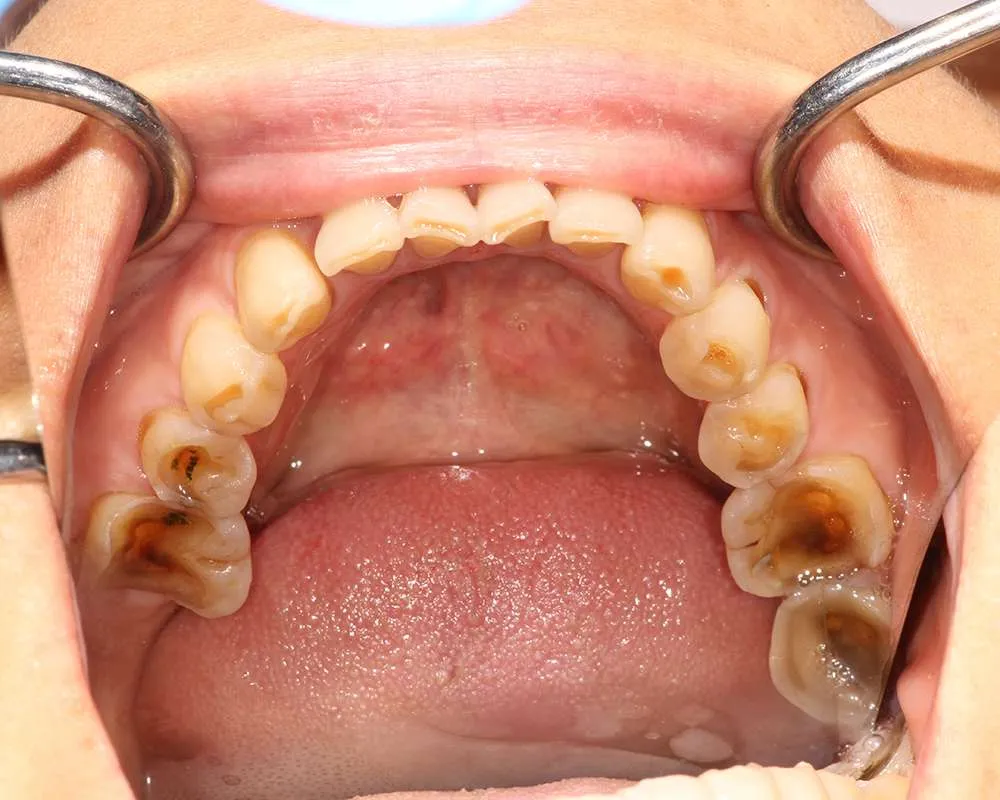

Real Stories, Real Results: Case Studies Showcasing How Our Personalized Approach Transforms Smiles and Lives

Witness the Remarkable Changes We Can Achieve